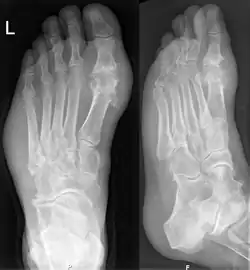

Dna na rentgenovém snímku levého chodidla: Typickým místem výskytu je kloub palce u nohy. Zasaženy jsou také měkké tkáně na podélné straně chodidla.

Dnu lze diagnostikovat a léčit bez dalších vyšetření u osob trpících hyperurikémií a klasickou podagrou. Pokud však jsou o diagnóze pochybnosti, měla by být provedena analýza synoviální tekutiny.[1] Rentgenové snímkování je pro stanovení diagnózy chronické dny velmi užitečné, u akutních záchvatů je však lze využít jen minimálně.[7]